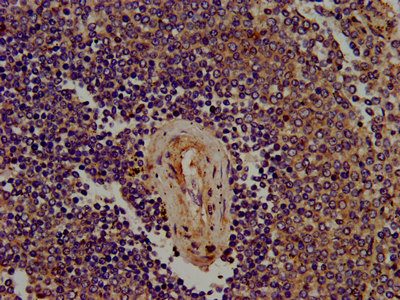

IHC image of CSB-PA842706LA01HU diluted at 1:400 and staining in paraffin-embedded human lymph node tissue performed on a Leica BondTM system. After dewaxing and hydration, antigen retrieval was mediated by high pressure in a citrate buffer (pH 6.0). Section was blocked with 10% normal goat serum 30min at RT. Then primary antibody (1% BSA) was incubated at 4°C overnight. The primary is detected by a biotinylated secondary antibody and visualized using an HRP conjugated SP system.